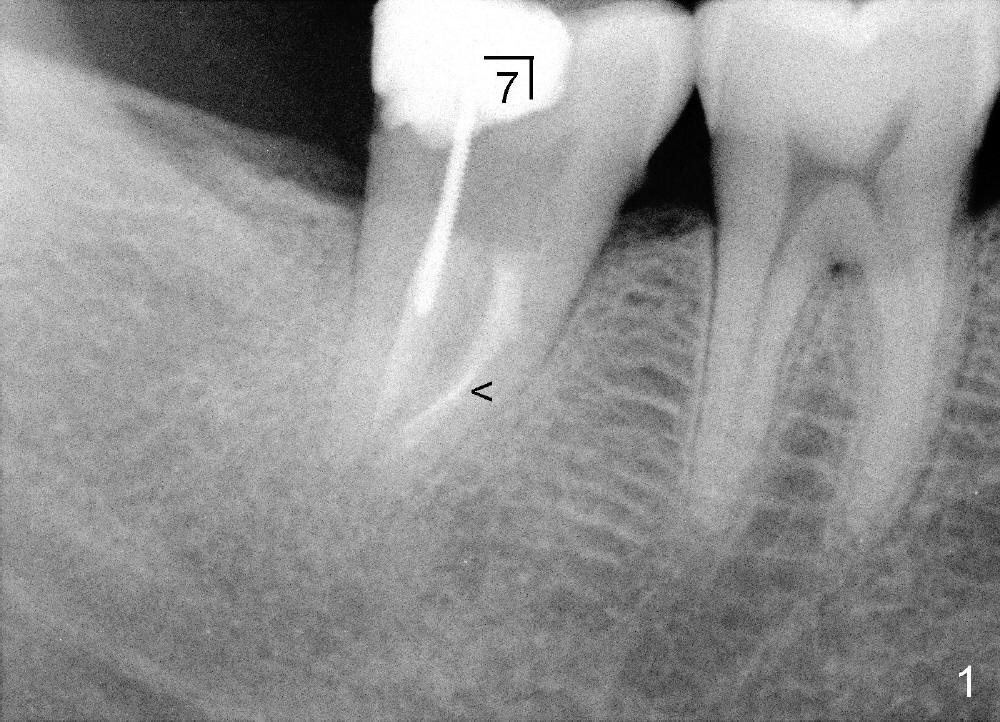

It is advantageous to place implant immediately or shortly (4-8 weeks) after extraction.  But most teeth to be extracted are potentially infected, such as in the case of Ms. Pei (Fig.1).  Periapical radiolucency (PARL) is not obvious prior to extraction. Six weeks post-extraction, osteotomy is finished with bone expansion and drilling (Fig.2 D, 5x14mm).  Tatum tapered implant is placed (Fig.3 I: 6x14). So far PARL is minimal if any (Fig.2,3 <).  Pain develops approximately 20 days post-implantation with expanding PARL (Fig.4 <).  Antibiotic treatment does not resolve the infection.  The implant has to be removed.  Infected granulation tissue is thoroughly removed from the apical portion of  the socket (Fig.5 <) with a curette (C).  Scaling and root planing is done for 4 quadrants.  A month later, potentially infected hard tissue is removed by reamers (Fig.6 D, 5 mm).  Bicon implant is buried inside the bone and separated from the oral cavity (Fig.7 I, 5x8).  At that time, there is a gap next to the implant (>).  Five months later, the gap disappears, suggesting implant osteointegration (Fig.8).  Extraoral cementation is done between abutment (A) and crown (C).  The abutment/crown unit is tapped into the implant with 2 visible threads (<).  The latter indicates that the abutment is completely seated.  Dashed lines in Fig.5-7 denote the upper border of the inferior alveolar canal.  PAs are taken 6 months (Fig.9) and 1 year 7 months (Fig.10) post cementation.  In all, it is a hassle to do re-implantation.  Efforts should be exerted to prevent post-implant infection.